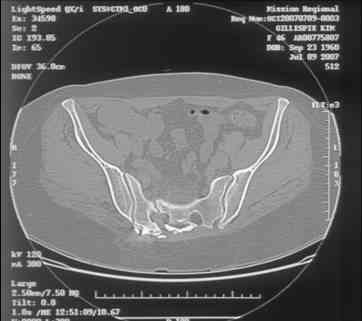

Here is a magnified view. Sorry about the quality but the CT was scanned into our system.

Thank you...it might help to remove the disengaged and other iliosacral screws then insert longer lag screws into the upper sacral segment and if anatomically feasible into the second sacral segment as well.

At this point, I'd ignore the right pubic root issue if asymptomatic.